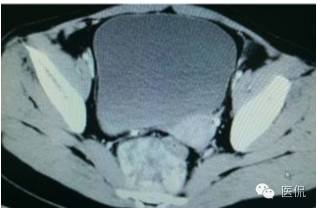

增强静脉期(CT值62HU)